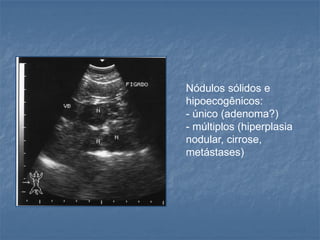

Nódulos sólidos e

hipoecogênicos:

- único (adenoma?)

- múltiplos (hiperplasia

nodular, cirrose,

metástases)